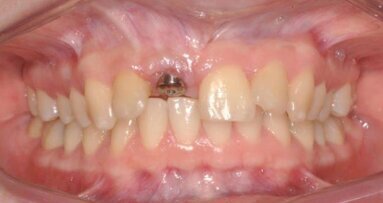

Do mojego gabinetu zgłosiła się 44-letnia pacjentka, u której na przestrzeni kilku lat trzykrotnie została wykonana resekcja korzenia zęba 22. Po każdym zabiegu dochodziło do odbudowywania się torbieli. Stan przed zabiegiem obrazują ryciny 1 i 2. Pacjentka została przysłana do mnie z rozpoczętą 3 dni wcześniej antybiotykoterapią, podany został Clindamicin a 600 mg 2 x 1. Pomimo rozpoczętej terapii antybiotykiem nadal utrzymywał się stan ropny. Jedynym rozwiązaniem było usunięcie korzenia wraz z koroną cyrkonową wykonaną na nim.

Korzeń został usunięty atraumatycznie przy użyciu urządzenia PiezoSurgery®. Na rycinie 3 pokazano stan po usunięciu zęba.